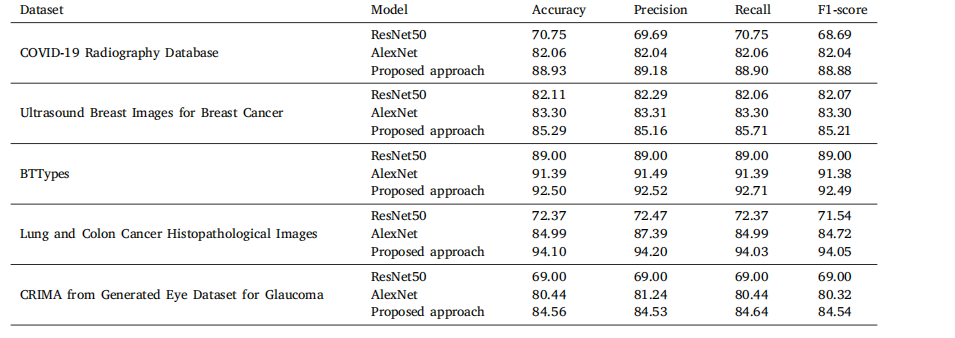

Table 14Classification performance of different noninterpretable approaches across multiple datasets

表14 不同非可解释性方法在多个数据集上的分类性能。